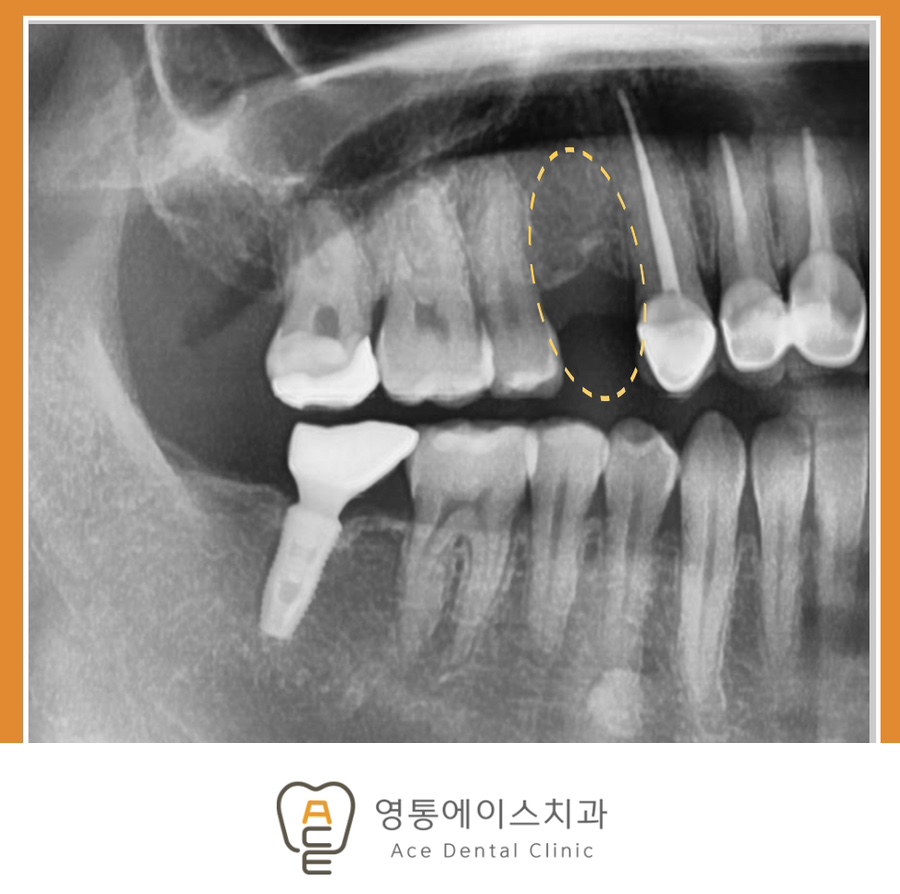

치료 전 사진 / 2025.08.07

치아를 상실한 부위를 방치하면 안 되는 이유에 대해 자세히 알아보겠습니다. 먼저, 저작 기능이 감소합니다. 치아 하나가 없어지면 음식을 씹는 능력이 현저히 떨어집니다. 특히 어금니가 상실된 경우, 단단한 음식을 씹기 더욱 어려워져 불편감이 생길 수 있죠.

다음으로는 발음의 문제입니다. 앞니 부분이 상실되는 경우 올바른 발음을 구사하기 힘들어질 수 있습니다. 치아는 혀와 함께 특정 소리를 내는 데 중요한 역할을 합니다. 또한 상실된 치아 주변의 치아는 빈 공간으로 이동하는 특징을 가지고 있습니다. 이런 현상이 생기게 되면, 치아 배열이 어긋나고 추후 교합 문제를 일으킬 수 있습니다.

그리고 상실된 치아를 방치하면 턱뼈 외 얼굴 형태의 변화가 일어납니다. 치아 뿌리가 없어지면 해당 부위의 턱뼈가 서서히 줄어들게 됩니다. 이로 인해 얼굴 형태에 변화를 줄 수 있습니다. 이러한 문제를 예방하거나 해결하기 위해서는 가능한 한 빨리 치과를 방문하여 적절한 치료를 받는 것이 중요합니다.